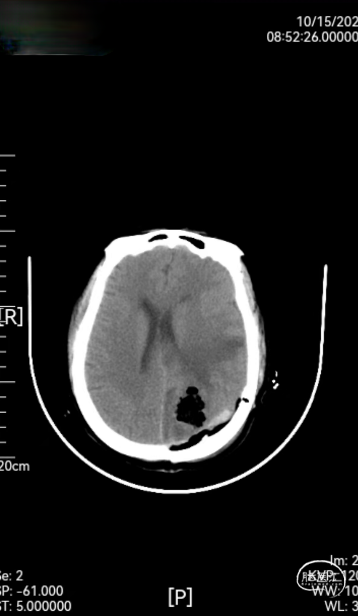

➤ 术后检查:术后第2天,第8天,第12天复查头颅CT(如图3),术后术区无渗血,骨瓣固定良好,无错位及膨出,且CT无伪影,患者顺利出院。

图3:术后第2天,第8天,第12天复查头颅CT